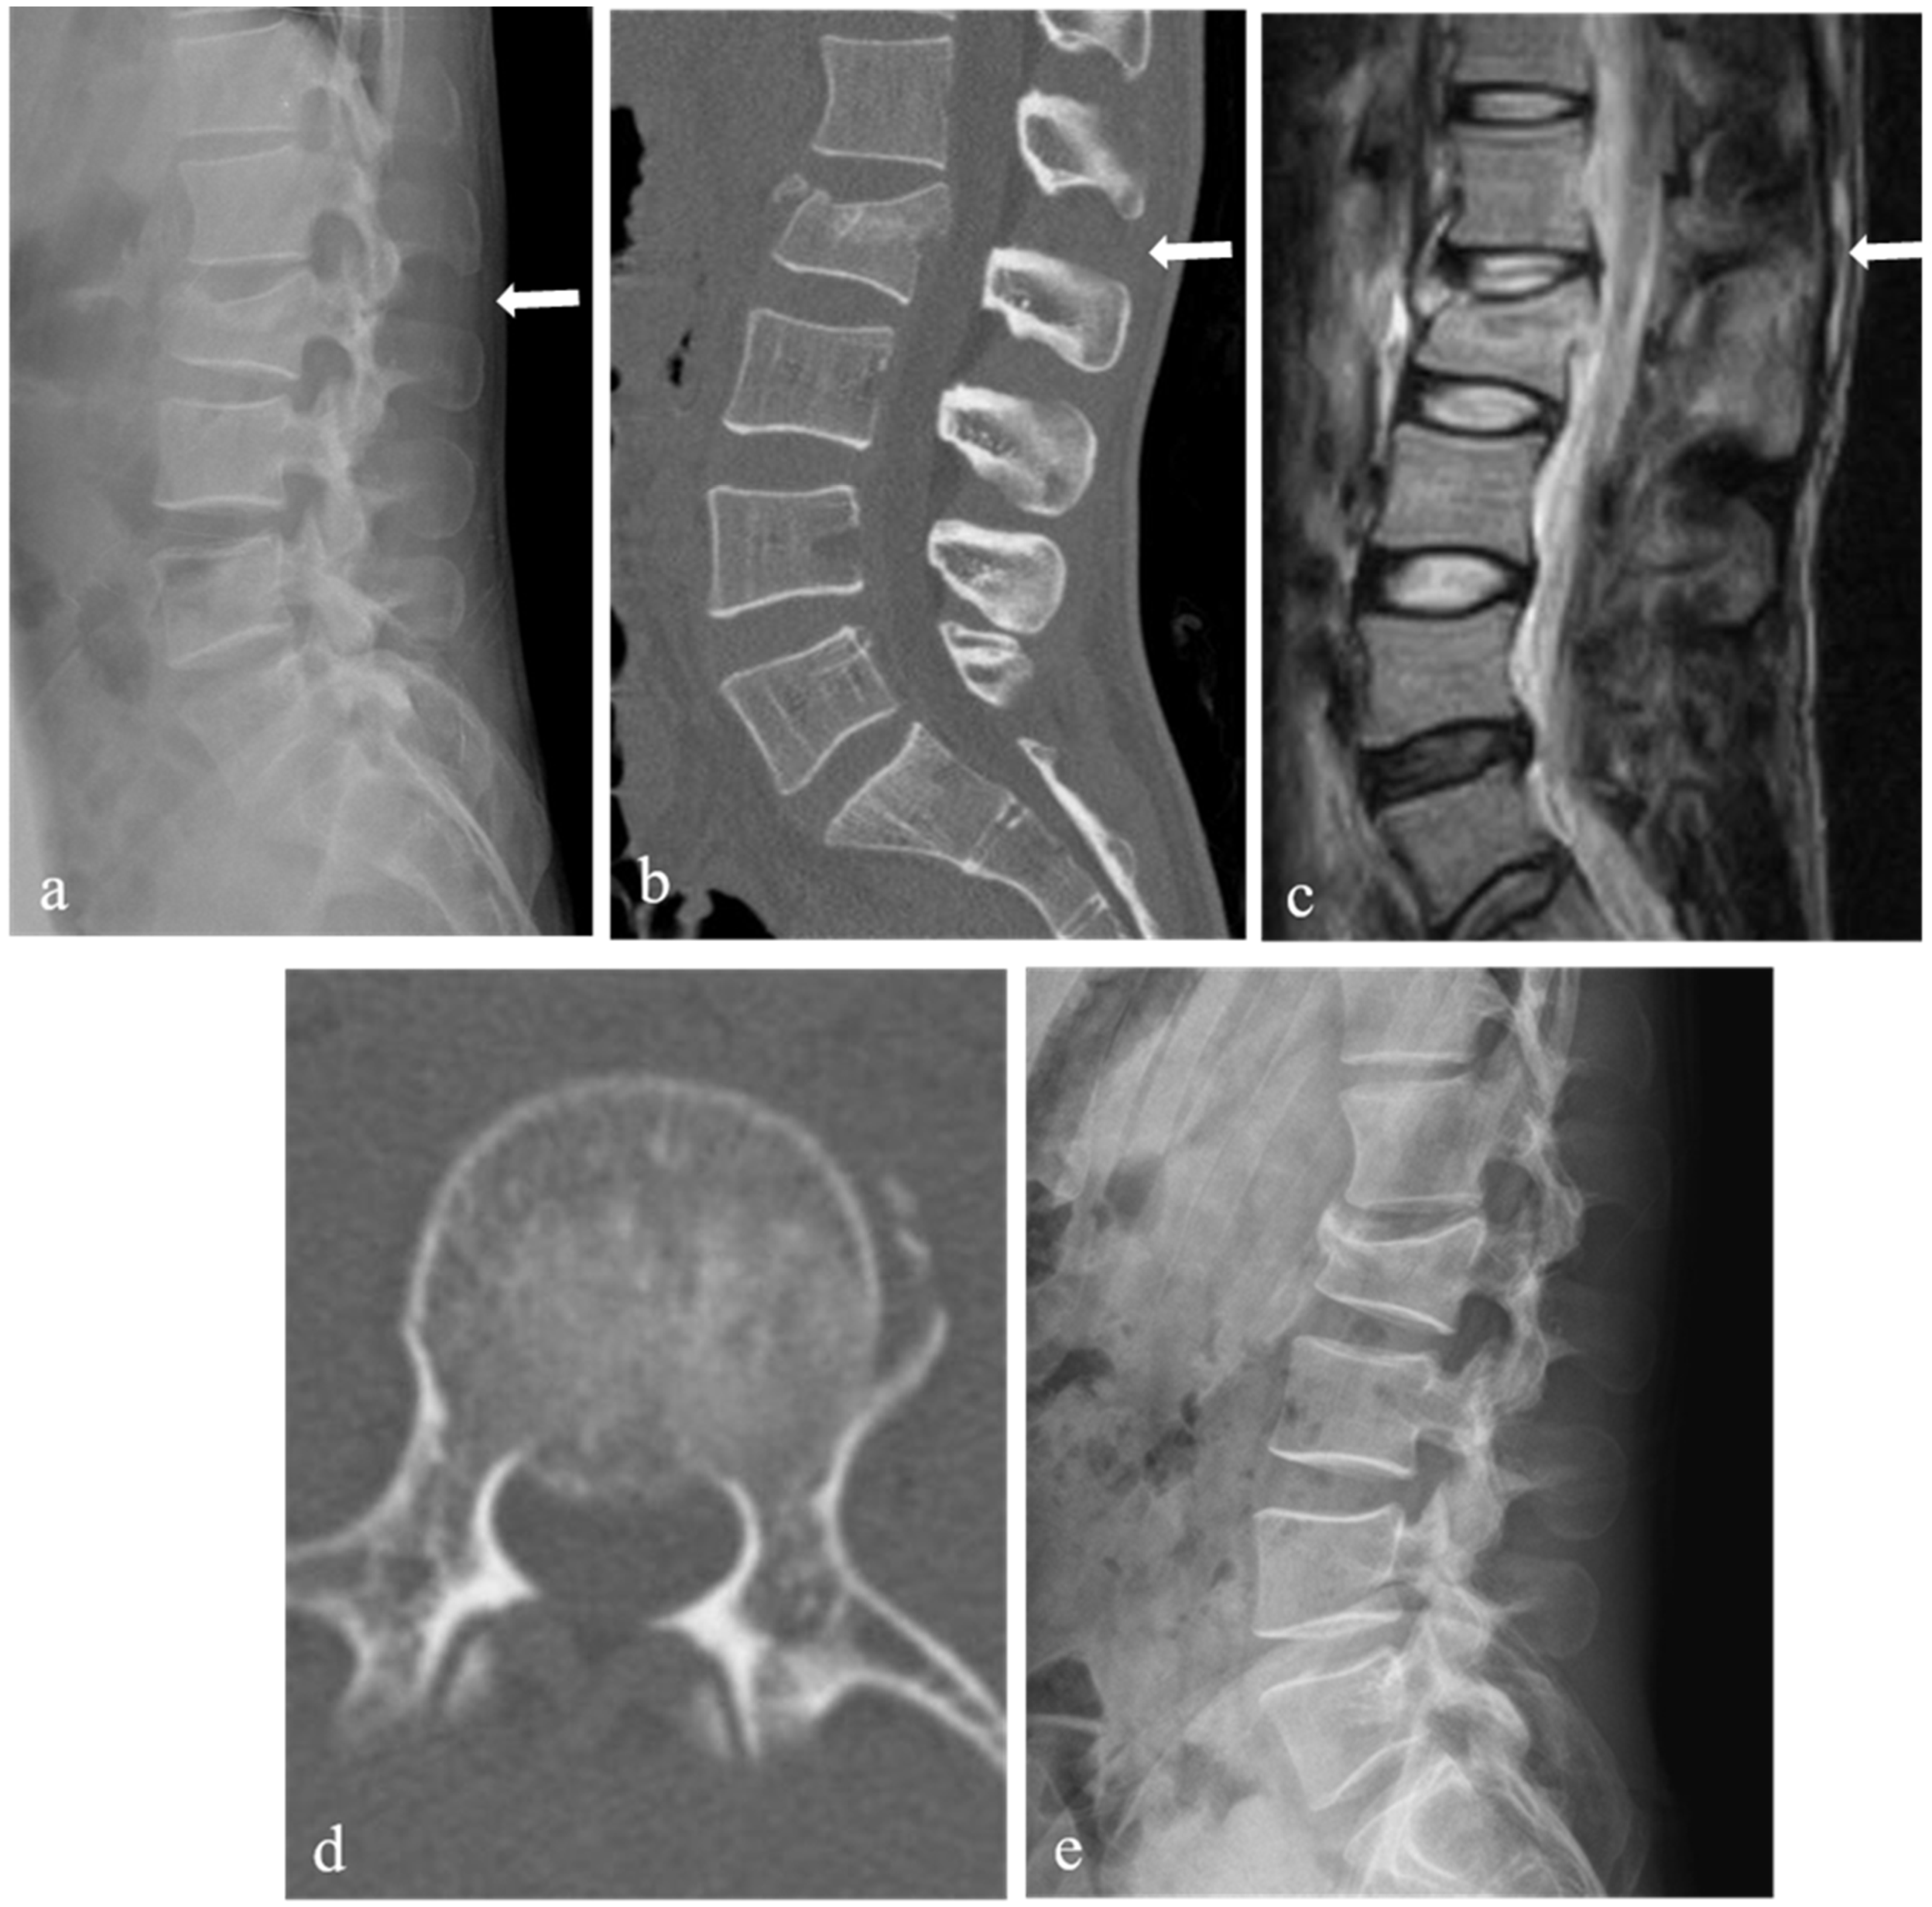

| Spinal canal compromise (%) ‡ | 27.9 ± 7.6 | 35.7 ± 13.3 | 0.03 |

| Loss of vertebral body height (%) ‡ | 28.6 ± 7.8 | 34.1 ± 6.0 | 0.01 |

| Kyphotic angle (°) ‡ | 10.1 ± 6.2 | 13.9 ± 5.0 | 0.04 |